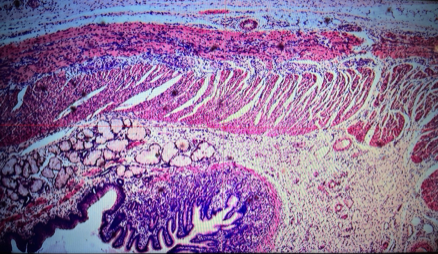

jejunum

villi

intestinal crypts

lumen

mucosa

mucosal epithelium

lamina propria

muscularis mucosa

submucosa

muscularis (externa)

serosa/adventitia